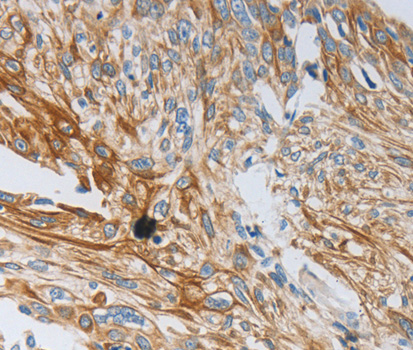

IHC (Immunohistochemisry)

(Figure 3. IHC analysis of CD101 using anti-CD101 antibody (AAA126484).CD101 was detected in a paraffin-embedded section of human lung cancer tissue. Heat mediated antigen retrieval was performed in EDTA buffer (pH 8.0, epitope retrieval solution). The tissue section was blocked with 10% goat serum. The tissue section was then incubated with 2 ug/ml rabbit anti-CD101 Antibody (AAA126484) overnight at 4 degree C. Peroxidase Conjugated Goat Anti-rabbit IgG was used as secondary antibody and incubated for 30 minutes at 37 degree C. The tissue section was developed using HRP Conjugated Rabbit IgG Super Vision Assay Kit with DAB as the chromogen.)